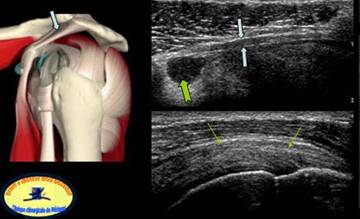

LIGAMENTUL HUMERAL TRANSVERS

Ligamentul humeral transvers→ prelungeste

fascia superficiala a suprascapularului→in

afara impiedecand astfel luxatia bicepsului

in timpul miscarilor de rotatie.